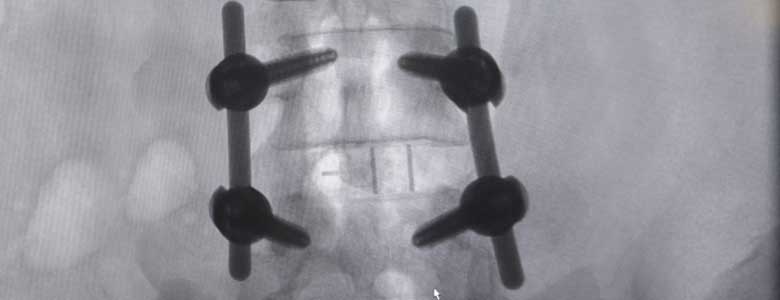

Cirugía de Columna

Cirugía de Columna La Cirugía de Columna se utiliza para aliviar el dolor y/o el entumecimiento que se asocia a este dolor, que... Más información